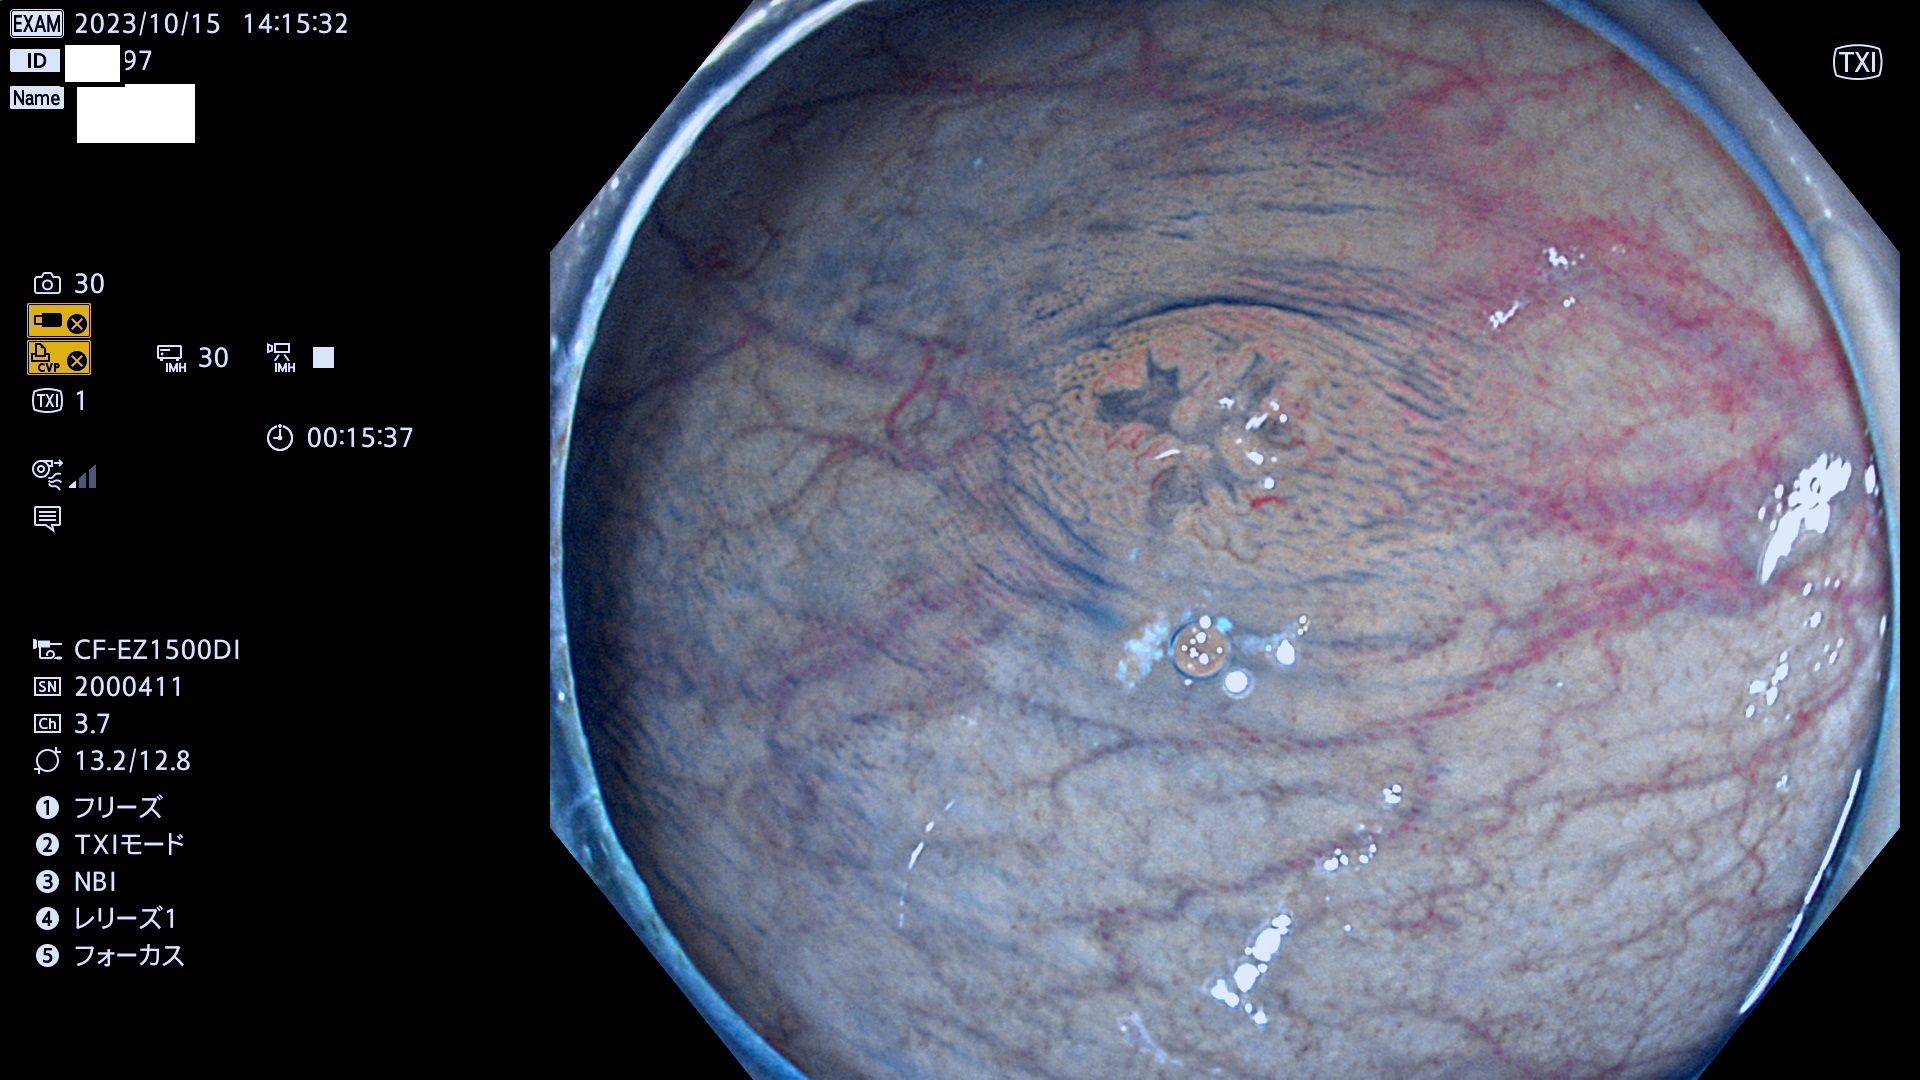

表面型腺腫(Flat Adenoma)の中で、完全に平坦な物をUb、陥凹している物をUcと呼びます。平坦隆起型(Ua)よりも、発見が難しく危険な病変です。このタイプは「内視鏡後・大腸癌の重要犯人」であり、この発見率は「腺腫発見率」よりも、重要な意味があります。

毎週の検査(木・金・土・日)に発見されたUb、Uc型・腺腫を、その週の日曜の夜にUPし1週間、提示します。

抽出の対象期間 2023年10月12日(木)〜10月15(日)の5日間(48件の検査)4件